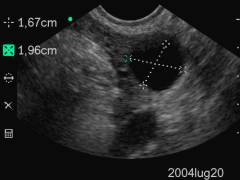

Data inserimento: 05 /04/2005Data esame: 01/04/2005 Strumento: Sonosite Età paziente: F 16 anni Diagnosi ecografica di gravidanza per la dimostrazione della camera gestazionale alla IV settimana di gestazione. Elaborazione digitale: Andrea Dini